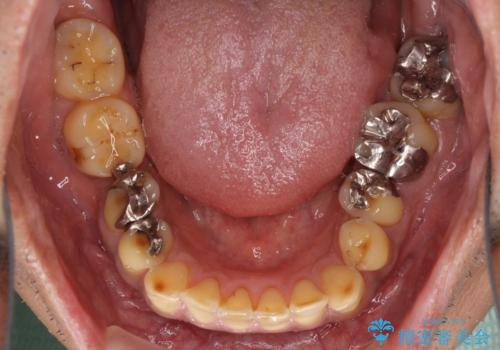

- すり減った前歯や奥歯の銀歯を気にして来院された患者様です。

骨格的な反対咬合により上顎前歯の先端が顕著にすり減っている状態でした。

奥歯の欠損が散見されており、銀歯の装着されている歯も多いため、ワイヤー矯正にて歯列を調整し、その後オールセラミッククラウンにて補綴治療を行うこととしました。

反対咬合改善には奥歯の咬み合わせをしっかりと改善させることが必要となりますが、奥歯に欠損が多いため、矯正治療が難航することが予想されます。